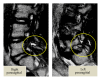

Spondylolysis is reported as a stress fracture of the pars interarticularis with a strong hereditary basis. Three cases of lumbar spondylolysis in juveniles from the same family are reported, and the genetics of the condition are reviewed. The first boy, a 13-year-old soccer player, was diagnosed with terminal stage L5 bilateral spondylolysis with grade 1 slippage. The second boy, a 10-year-old baseball player, had terminal stage right side unilateral spondylolysis. The third boy, also a 10-year-old baseball player, was diagnosed with early stage bilateral L5 spondylolysis. The second and third boys are identical twins, and all three cases exhibited concomitant spina bifida occulta. Lumbar spondylolysis has a strong hereditary basis and is reported to be an autosomal dominant condition.